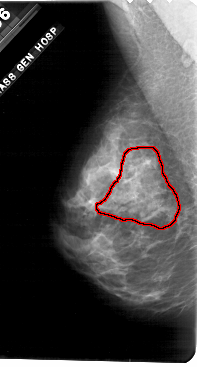

A_1698_1.LEFT_CC

FILE: A_1698_1.LEFT_CC.OVERLAY

TOTAL_ABNORMALITIES 1

ABNORMALITY 1

LESION_TYPE CALCIFICATION TYPE PLEOMORPHIC DISTRIBUTION SEGMENTAL

ASSESSMENT 5

SUBTLETY 4

PATHOLOGY MALIGNANT

TOTAL_OUTLINES 1

BOUNDARY